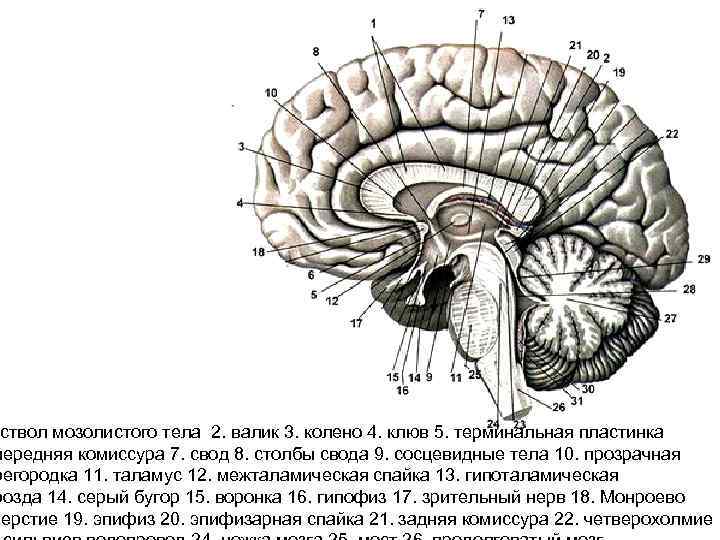

ствол мозолистого тела 2. валик 3. колено 4. клюв 5. терминальная пластинка передняя комиссура 7. свод 8. столбы свода 9. сосцевидные тела 10. прозрачная регородка 11. таламус 12. межталамическая спайка 13. гипоталамическая розда 14. серый бугор 15. воронка 16. гипофиз 17. зрительный нерв 18. Монроево верстие 19. эпифиз 20. эпифизарная спайка 21. задняя комиссура 22. четверохолмие

ствол мозолистого тела 2. валик 3. колено 4. клюв 5. терминальная пластинка передняя комиссура 7. свод 8. столбы свода 9. сосцевидные тела 10. прозрачная регородка 11. таламус 12. межталамическая спайка 13. гипоталамическая розда 14. серый бугор 15. воронка 16. гипофиз 17. зрительный нерв 18. Монроево верстие 19. эпифиз 20. эпифизарная спайка 21. задняя комиссура 22. четверохолмие